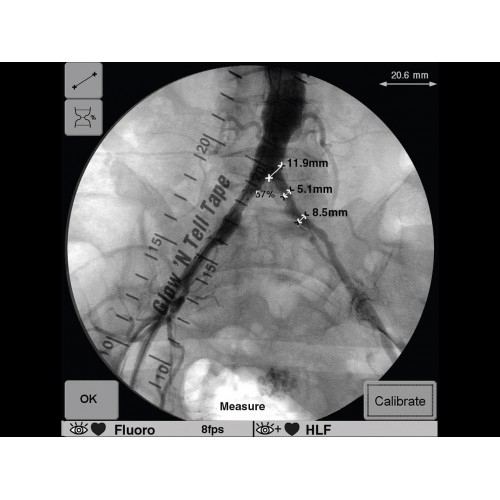

GE OEC 9900 Elite оснащен революционной системой визуализации, обеспечивающей кристально четкое изображение анатомических структур. Интеллектуальная система автоматически адаптирует параметры исследования под конкретную хирургическую задачу, обеспечивая оптимальный баланс между качеством изображения и лучевой нагрузкой. Особое внимание уделено удобству работы операционной бригады.

В ведущих медицинских центрах GE OEC 9900 Elite успешно применяется для проведения сложных кардиологических, нейрохирургических и ортопедических вмешательств. Система доказала свою эффективность при выполнении стентирования коронарных артерий, эмболизации сосудов головного мозга и вертебропластики. Многие учреждения отмечают повышение качества операций после внедрения этого оборудования.